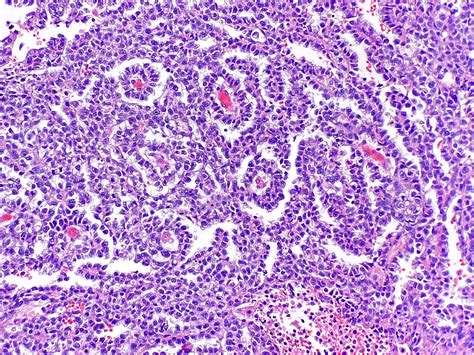

Histopathology of Yolk Sac Tumor

Schiller Duval Bodies are distinctive, glomeruloid structures found within yolk sac tumors. These bodies are named after the pathologists who first described them, Schiller and Duval. They are composed of a central blood vessel surrounded by a layer of tumor cells, which in turn are enclosed by a layer of connective tissue. The unique morphology of Schiller Duval Bodies makes them a reliable marker for the diagnosis of yolk sac tumors.

These features collectively contribute to the glomeruloid appearance of Schiller Duval Bodies, which is a hallmark of yolk sac tumors.

The presence of Schiller Duval Bodies is highly indicative of yolk sac tumors. These tumors are part of a broader category of germ cell tumors, which can occur in both gonadal and extragonadal sites. The identification of Schiller Duval Bodies in a biopsy specimen is often sufficient to confirm the diagnosis of a yolk sac tumor, guiding subsequent treatment decisions.